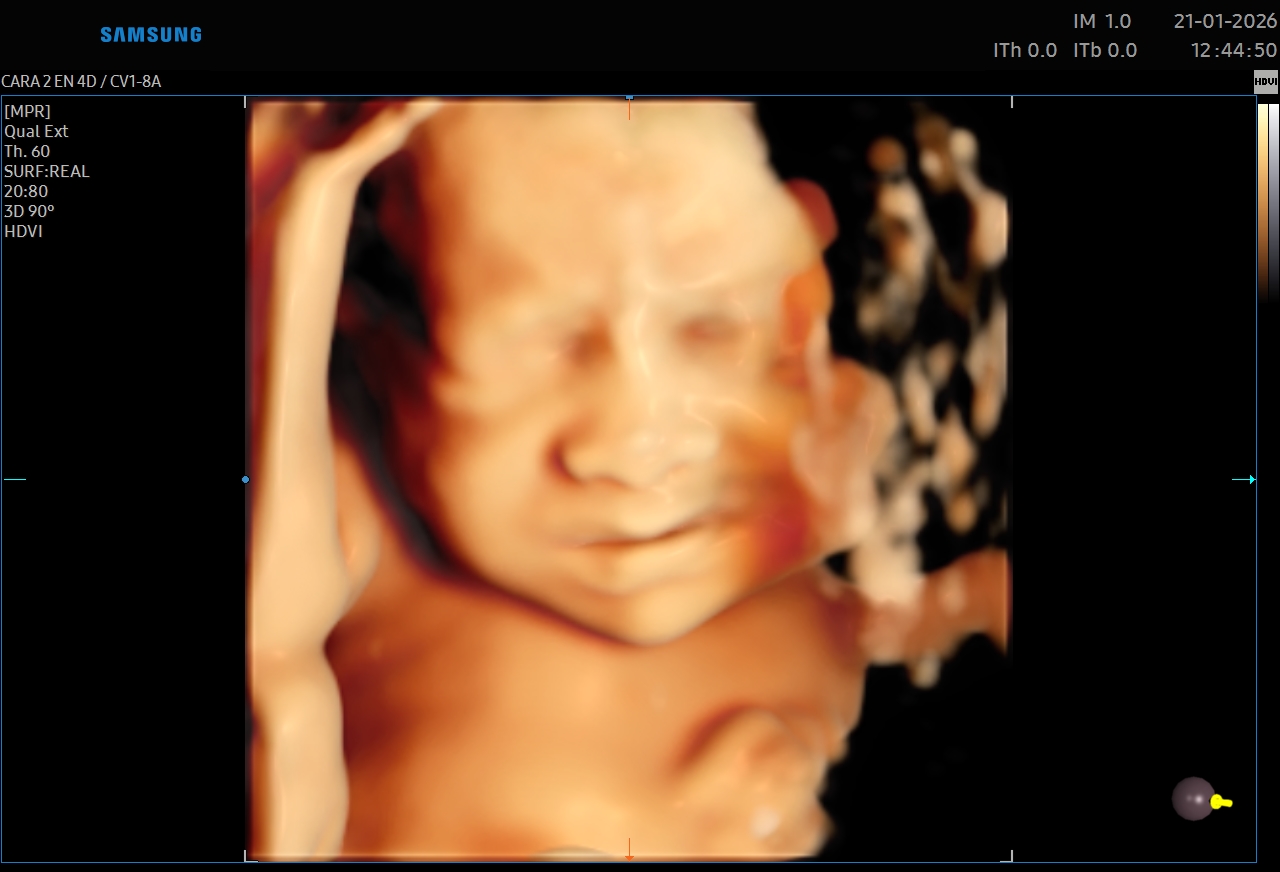

Ecografías 5D

La ecografía 5D es una experiencia única que te permite ver a tu bebé con un nivel de realismo sorprendente, capturando detalles como sus gestos, expresiones y movimientos en tiempo real.

Gracias a esta tecnología avanzada, podrás observar el rostro de tu bebé con mayor claridad, creando un vínculo emocional aún más especial antes de su nacimiento. Es el momento perfecto para compartir con tu familia y guardar recuerdos inolvidables de esta etapa tan importante.

Además de ser una experiencia hermosa, este estudio se realiza con equipos de alta tecnología y bajo supervisión médica, garantizando seguridad tanto para la mamá como para el bebé.